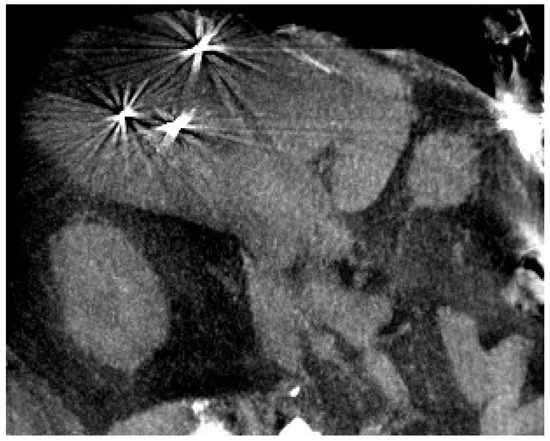

- Ritter, A.; Bruners, P.; Isfort, P.; Barabasch, A.; Pfeffer, J.; Schmitz, J.; Pedersoli, F.; Baumann, M. Electroporation of the liver: More than 2 concurrently active, curved electrodes allow new concepts for irreversible electroporation and electrochemotherapy. Technol. Cancer Res. Treat. 2018, 17, 1533033818809994. [Google Scholar] [CrossRef]

- Pavliha, D.; Kos, B.; Marčan, M.; Županič, A.; Serša, G.; Miklavčič, D. Planning of Electroporation-Based treatments using Web-Based Treatment-Planning Software. J. Membr. Biol. 2013, 246, 833–842. [Google Scholar] [CrossRef] [PubMed]

- Esmaeili, N.; Friebe, M. Electrochemotherapy: A review of current status, alternative IGP approaches, and future perspectives. J. Healthc. Eng. 2019, 2019, 2784516. [Google Scholar] [CrossRef] [PubMed]